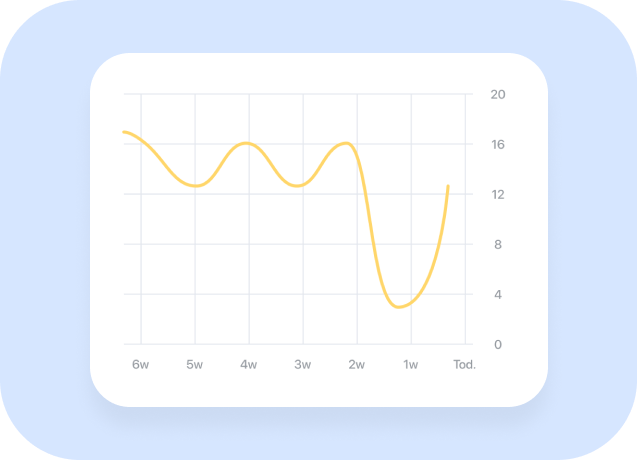

Konectom is leveraging data collected by the sensors available in the smartphone and compatible wearables to allow for quantitative and unbiaised analysis of neurological functions

Konectom is leveraging data collected by the sensors available in the smartphone and compatible wearables to allow for quantitative and unbiaised analysis of neurological functions